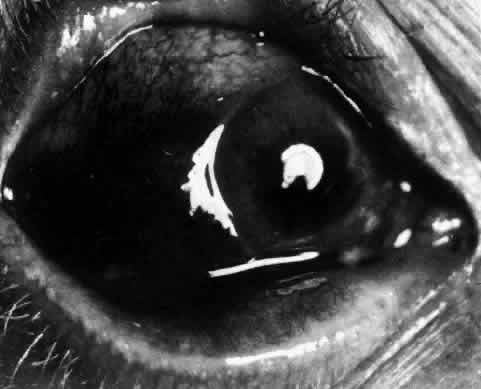

The redness of simple episcleritis may be intense, varying from a fiery-red or a brick-red discoloration to a mild red flush, but it does not have the bluish tinge that is seen in scleritis. The distribution is usually sectorial but can involve the whole anterior segment of the globe. The episcleral vessels are engorged but retain their normal radial position and architecture (Figs. 13 and 14; Color Plate 1A). In simple episcleritis, there is a diffuse edema of the episcleral tissues. These tissues are sometimes infiltrated with gray deposits that appear yellow in red-free light. Surprisingly, the eye is rarely tender to the touch.

In contrast to simple episcleritis, the infiltration and edema of nodular episcleritis are localized to one part of the globe, forming a nodule and some surrounding congestion (Color Plate 1B). The nodule can be moved over the underlying sclera, which is not edematous. The scleral plexus of vessels can be distinguished deep to the nodule, lying flat on the sclera and slightly congested but otherwise normal in color and configuration (Figs. 15 and 16). Episcleral nodules may be single or multiple but do not undergo necrosis (see Fig. 16). After multiple attacks of nodular episcleritis in the same location, the superficial lamellae of the sclera show some alteration and become slightly more transparent in this one area.